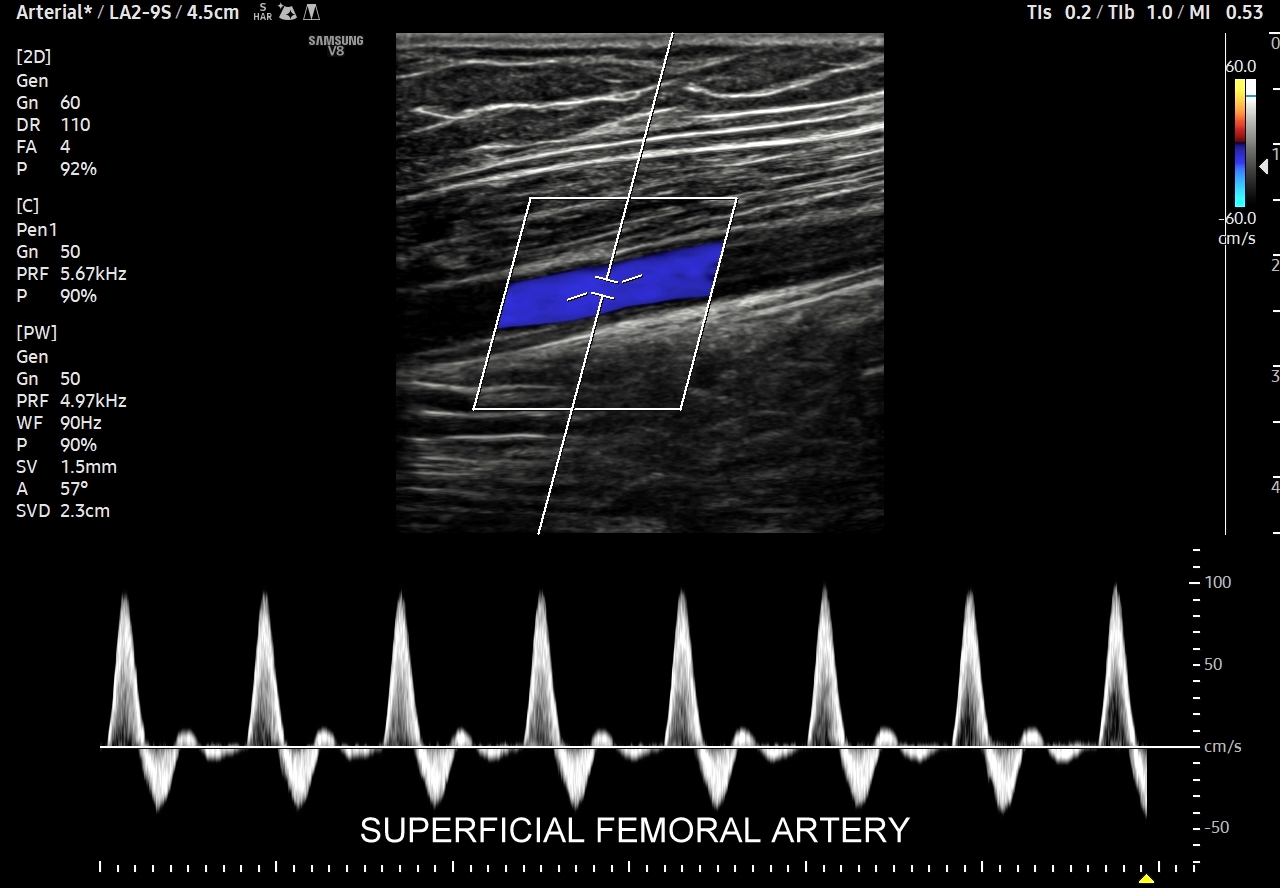

41. Patologie tętnic kończyn dolnych, w tym miażdżyca zarostowa, niedrożności, krążenie oboczne, tętniaki, urazy i rozwarstwienia.

- Badanie USG Doppler tętnic kończyn dolnych.